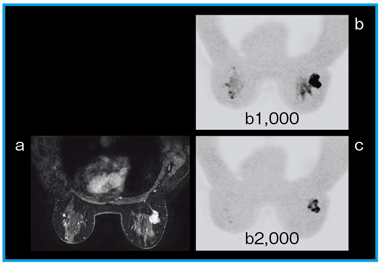

●胸部(図4)

通常,3Tの乳腺MRIは歪みの影響を受けるが,Discovery MR750w 3.0Tでは従来の3Tに比べて,磁場の歪みの影響を受けにくくなっている。

図4 乳房の浸潤性腺管癌

a:VIBRANT (1.0mm/−0.5mm,スキャン時間1分1秒)

b,c:DWI(multi-b,スキャン時間2分54秒)